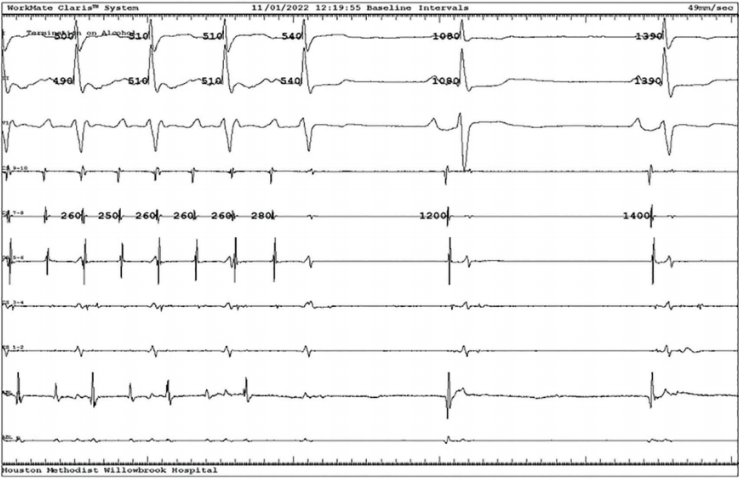

Following the initial approach of endocardial mitral ablation, alcohol VOM ablation was then performed (Figure 2). Remarkably, AFL terminated during the first injection of alcohol, indicating the effectiveness of the procedure in real time (Figure 3). A total of 10 cc of alcohol was injected into the VOM. Subsequently, a mitral isthmus conduction time of 151 msec was achieved, suggesting complete block.